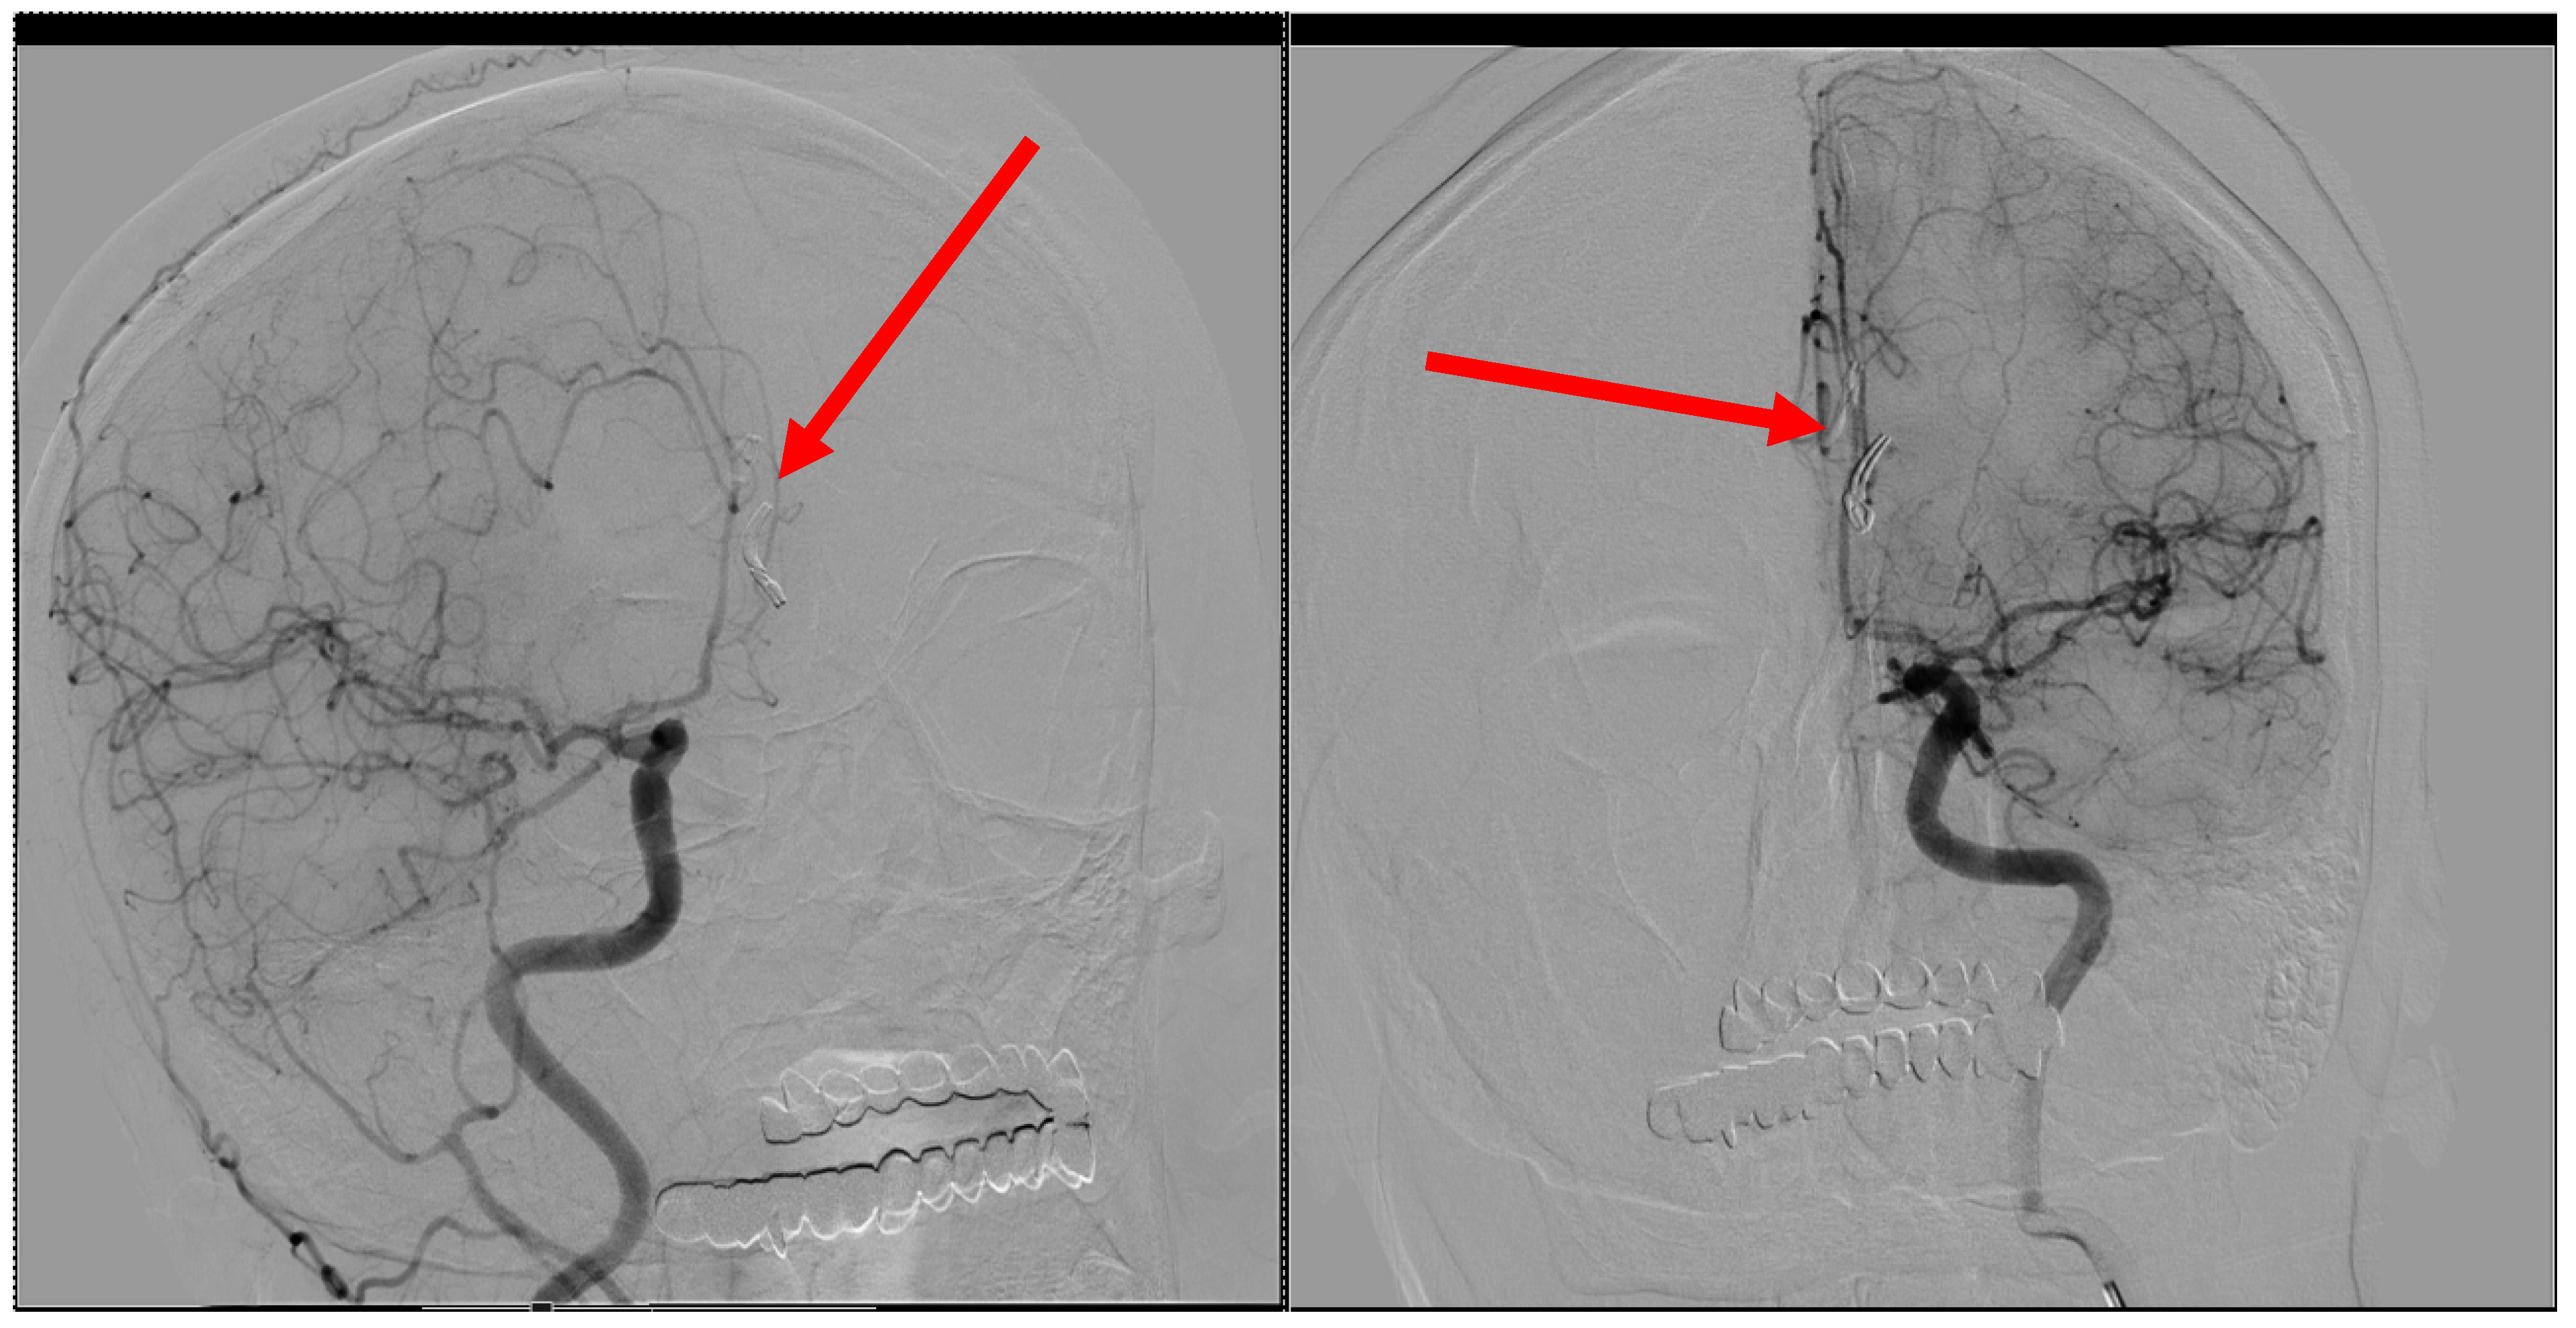

2. Case Presentation